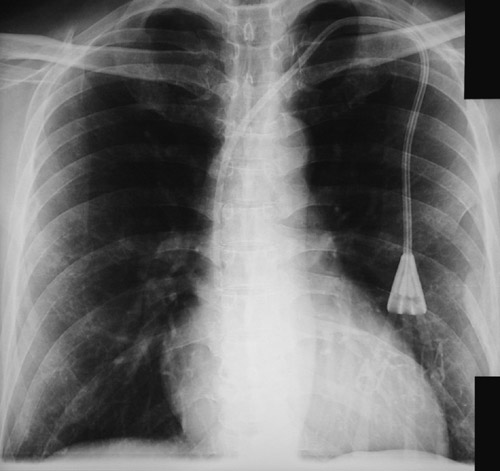

This chest radiograph shows the proper position for a central line placed through the right subclavian vein that passes into the superior vena cava down to the right atrium. A central line can be used to monitor fluid status and cardiac function.